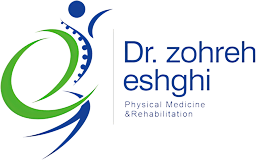

درد داخل ساق پا

درد در قسمت داخلی ساق پاها مربوط به ماهیچه های عمیق ساق پا مانند تیبیالیس خلفی (به آن شین اسپلینت خلفی نیز گفته می شود) است.

درمان این درد که معمولا به تدریج و با افزایش سطح فعالیت ایجاد می شود، آسان نیست.

علت بیشتر موارد درد قسمت داخلی ساق پا، التهاب تاندون، تحت فشار قرار گرفتن استخوان، سندرم کمپارتمان یا گیر افتادن عصب می باشد.

درد جلوی ساق پا

در فعالیت های پربرخورد یا با تغییرات ناگهانی در سطح فعالیت، معمولا جلوی ساق پا درد می گیرد.

درد شین اسپلینت در میان دوندگان و سایر ورزشکاران، زیاد اتفاق می افتد و دلیل آن کشیدگی و التهاب تیبیالیس قدامی (ماهیچه درشتنئی پیشین) است.

شین اسپلینت

نام دیگر شین اسپلینت سندرم استرس تیبیا میانی است، شین اسپلینت یکی از دلایل احتمالی درد شدید ساق پا می باشد.

سندرم استرس تیبیا به درد و التهاب تاندونها و ماهیچههای متصل شده به استخوان ساق پا (درشت نی) و تیبیالیس قدامی اشاره دارد.

این نوع آسیب به دلیل استفاده زیاد و مداوم از این ماهیچه ها هنگام دویدن یا سایر تمرینات پربرخورد رخ می دهد.

کسانی که توازن بدنی نامناسب و عدم تعادل عضلانی دارند، بیشتر دچار شین اسپلینت می شوند.